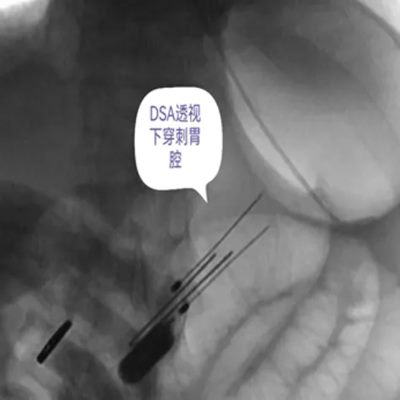

DSA引导下经皮胃造瘘术,是在数字减影血管造影(DSA)这个“透视眼”的实时可视化导航下,于患者腹壁上建立一个仅 3-5毫米 的微小穿刺点。通过这个“针眼”,医生精准地将一根营养管直接置入胃部,建立起一条直达的营养通道。

整个过程就像一次精准的“导航穿刺”,全程操作便捷、创伤小,却能完美替代传统的鼻饲管,为患者提供长期、稳定、安全的营养支持。

医院临床实践中就有典型案例:一名65岁食道癌伴淋巴结转移患者,因食道狭窄无法插入胃镜,且体质虚弱难以耐受全麻手术,团队借助DSA精准导航,仅用10分钟便完成手术,局部麻醉下患者全程无明显不适,术后1天即可通过造瘘管补充营养,为后续抗肿瘤治疗顺利开展奠定了坚实基础。